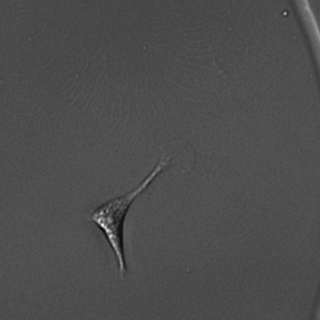

3.3.4 Osteoclasts segmentation

Osteoclasts are responsible for bone resorption, and are widely studied (see Labour et al. (2016) for instance) as being responsible for certain pathologies such as osteoporosis when dysfunctional. Their differentiation goes through several stages, culminating in the activated osteoclast. The latter is generally large and contains numerous nuclei. Atlantic Bone Screen (ABS) company is investigating the effect of different drugs in inducing either proliferation or cell death in these activated osteoclasts, in order to regulate their population. To do so, they extract osteoclasts from biopsies, culture them, apply the drugs and image them under a bright-field microscope.

The studied image is a crop of an image containing around 20,000 cells. We can see touching cells presenting a great variety in size, shape color. The image is complex to segment and poses a real challenge. What is more, ABS does not want to count pre-osteoclasts (small black nuclei), but only the mature cells (according to specific nuclei criteria). Each study comprises around sixty images, hence manual counting task performed at ABS is costly and laborious.

In Figure 7, we present a qualitative depiction that underscores the enhancement in segmentation accuracy attained through transfer learning with just a few labels. Labeling required approximately 2 minutes, while the training process took about 5 minutes. A quantitative comparison is available in Figure 7(l).